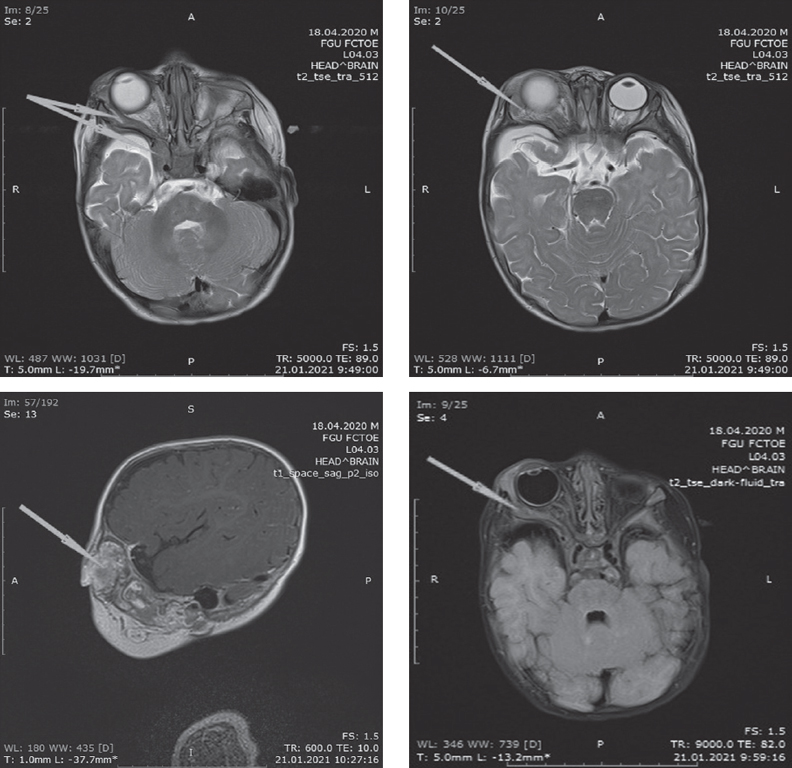

The article describes a clinical case of familial neurofibromatosis type I. This diagnosis was made in a nine-month-old patient according to the diagnostic criteria recommended by the International Expert Committee on Neurofibromatosis. Clinicaly, there were hyperpigmented café-au-lait spot on the skin, the presence of one plexiform neurofibroma, the father had a genetically confirmed diagnosis of neurofibromatosis type I. Also after birth, this patient was diagnosed with buphthalmos.

A mutation in the Neurofibromin gene NFI leads to increased cell proliferation, with a rapidly progressive course, characterized by combined damage to the skin, eyes, nervous system and some internal organs, leading to neuroectodermal and mesodermal dysplasia. Neurofibromin is an intracellular protein in the human genome that regulates several pathways of growth control and plays a key role in the pathogenesis of congenital glaucoma associated with neurofibromatosis type I and plexiform neurofibroma. Plexiform neurofibroma originates from the sheaths of the peripheral nerves, often affects multiple nerves, is abundantly perfused, and is a benign neoplasm, but there is a lifelong risk of malignancy. On the other hand, congenital glaucoma is a relatively rare disease, usually due to infiltration of the anterior chamber angle by neurofibromas, closure of the angle by neurofibromatous-thickened ciliary body and choroid, fibrovascularization. The clinical picture of neurofibromatosis type I can be very variable, even among members of the same family. Under the influence of a combination of pathogenetic factors, an asymptomatic course is determined in one individual, while in another, the disease proceeds in a severe form, up to disability.

Surgical treatment for isolated orbital plexiform neurofibroma is used to decompress the orbit and prevent malignancy of the tumor. It should be noted that due to the peculiarity of the structure of the tumor, its total removal is often not possible. In this case, mini-frontal access was used.

After the intervention, exophthalmos regressed, ophthalmotonus returned to normal. The child was discharged in a satisfactory condition.

Thus, the described clinical case is of particular interest, based on the combination of orbital plexiform neurofibroma and congenital glaucoma associated with neurofibromatosis type I.